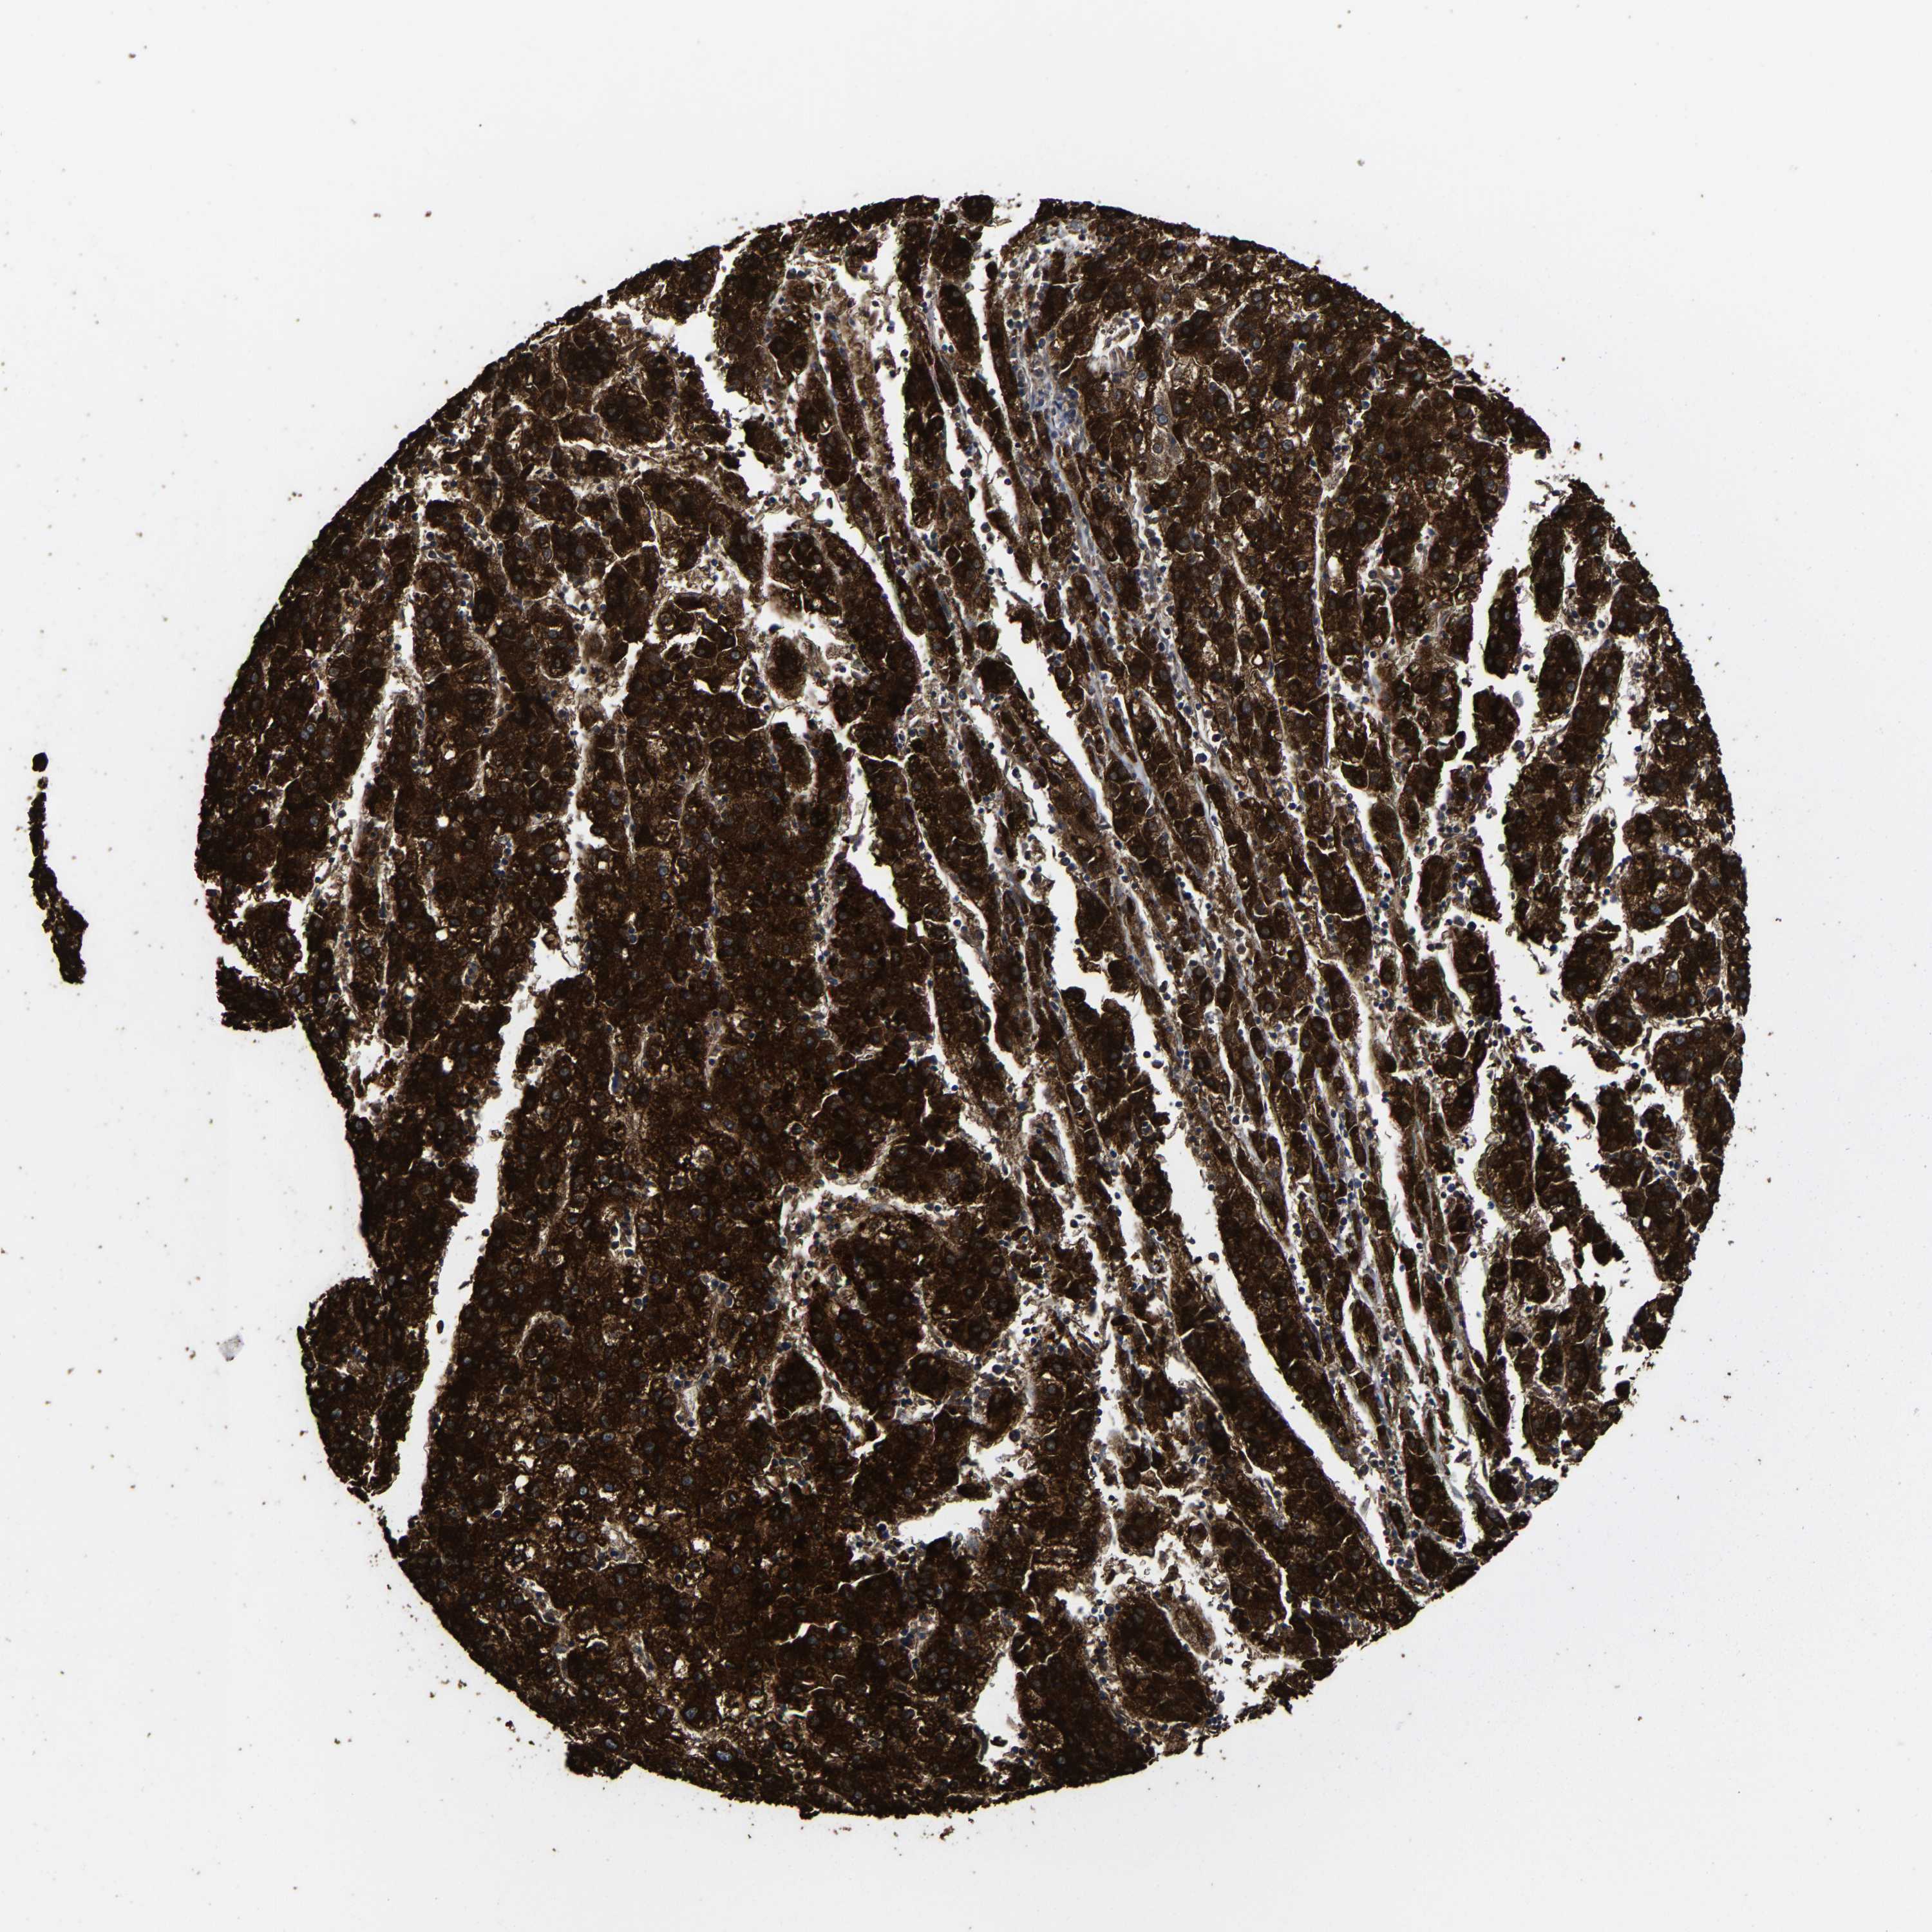

LIVER CANCER